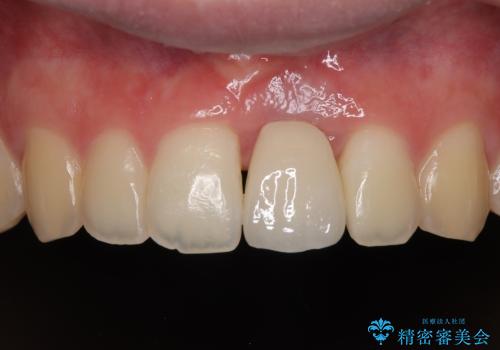

歯根吸収した前歯 短期間でのインプラント治療

- 前歯のインプラント治療を希望して来院された患者様です。

小学生の時に前歯を殴打したとのことで、歯根が吸収してしまい、抜歯が必要と判断されました。

長い間歯肉が炎症を患っていたため、炎症改善後には歯肉がやや退縮した状態となっていました。

歯肉移植により歯肉形態を改善するプランも提案しましたが、十分な仕上がりとのことで、大変満足していただけました。